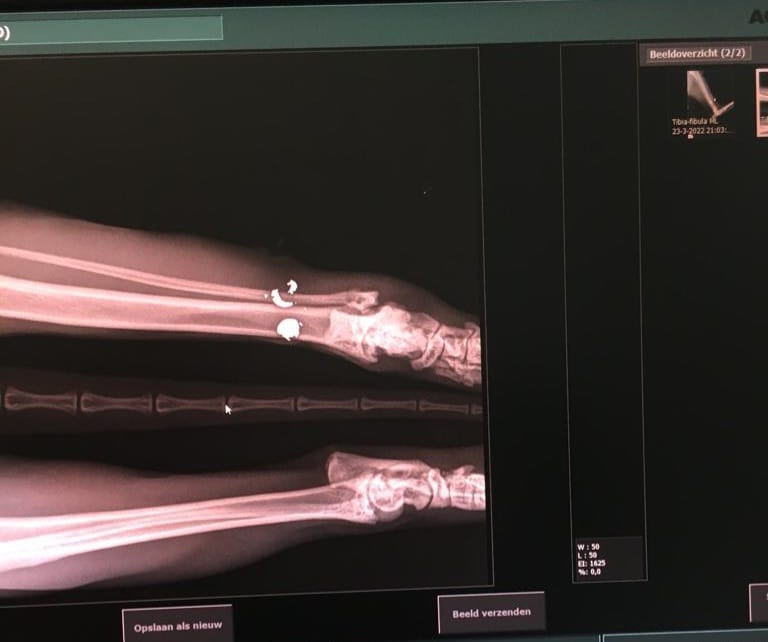

NIEUWAAL – Een wel heel laffe daad vorige week in de Willem Kesteloostraat in Nieuwaal. Marlies Oudenalder trof vorige week woensdag haar Main Coon kater Slayer in een plas bloed aan in haar slaapkamer. Slayer bleek een kogel in zijn poot te hebben die door de kracht van het schot zelfs versplinterd bleek te zijn. Eigenaar van de poes Marlies Oudenalder die inmiddels het incident heeft gemeld bij de politie heeft geen idee wie verantwoordelijk is voor de actie, maar hoopt wel dat iemand iets gezien heeft en dit bij de politie bekend wil maken. “Ik woon nu ruuim 9 jaar met heel veel plezier in Nieuwaal, maar daar is de 23e maart een heel abrupt einde aangekomen” aldus de aangeslagen eigenaresse van de kater. De kater is op woensdagavond 23 maart tussen 18.30 uur en 20.00 uur beschoten, waarschijnlijk in de buurt van de Willem Kesteloostraat of het Pauwenhofstraatje.

Diverse buurbewoners hebben inmiddels verontwaardigd gereageerd op het voorval waarbij iedereen aangeeft totaal geen overlast te hebben van de 10 kilo zware Main Coon kater. Er zijn zelfs mensen die aangeven blij te zijn met de aanwezige kater omdat hij veel muizen en zelfs ratten in de buurt vangt. Naast het aller belangrijkste voor Marlies de hoop dat Slayer weer snel zal opknappen lopen ook de kosten die ze moet maken voor de dierenarts behoorlijk op. Ze heeft nu al een bedrag van 450 euro moeten overmaken, en dat zal de komende weken vanwege de nazorg nog flink gaan oplopen, maar dat is het minst belangrijk aldus Marlies, die ook aangeeft graag te willen weten wie tot zoiets in staat is. Het zou dan ook fijn zijn dat als iemand iets gezien heeft of dat hij of zij weet wie de daders zijn dit bij de politie gaan melden. Dat kan via 09-8844 of via MisdaadAnoniem via 0800-7000 Met Slayer gaat het bijna een week later naar omstandigheden goed. Ze is verzorgd door dierenkliniek en krijgt nu pijnstillers en antibiotica. Volgens de dierarts mogen ze nog van geluk spreken dat de kater in zijn poot geraakt is en niet ergens anders in zijn lichaam, want dan had hij het waarschijnlijk niet overleeft.